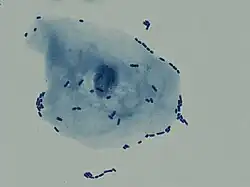

Zapalenie pęcherza moczowego – najczęstszy, przeważnie bakteryjny stan zapalny dróg moczowych, dotyczy błony śluzowej pęcherza moczowego. Najczęstszym patogenem jest pałeczka okrężnicy (Escherichia coli) oraz inne bakterie jelitowe, szczególnie z rodzajów: Staphylococcus i Enterococcus[1]. Zapalenie często dotyczy seksualnie aktywnych kobiet w wieku 20–50 lat i dlatego inną nazwą tego stanu jest "zapalenie pęcherza miodowego miesiąca".